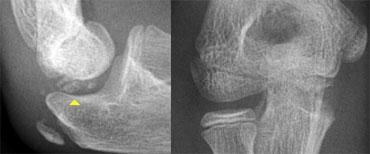

Normal medial epicondyle projecting posteriorly. Notice radial head dislocation and olecranon fracture

Nó nằm ở phía sau của khuỷu tay.

Trên hình chiếu thẳng bên, đặc biệt nếu cánh tay ở tư thế xoay trong, nó có thể chiếu ra phía sau đến mức có thể gợi ý một tổn thương bong điểm bám (hình ảnh).

Tuy nhiên, các tổn thương bong điểm bám thường nằm ở vị trí xa hơn và phía trước hơn.